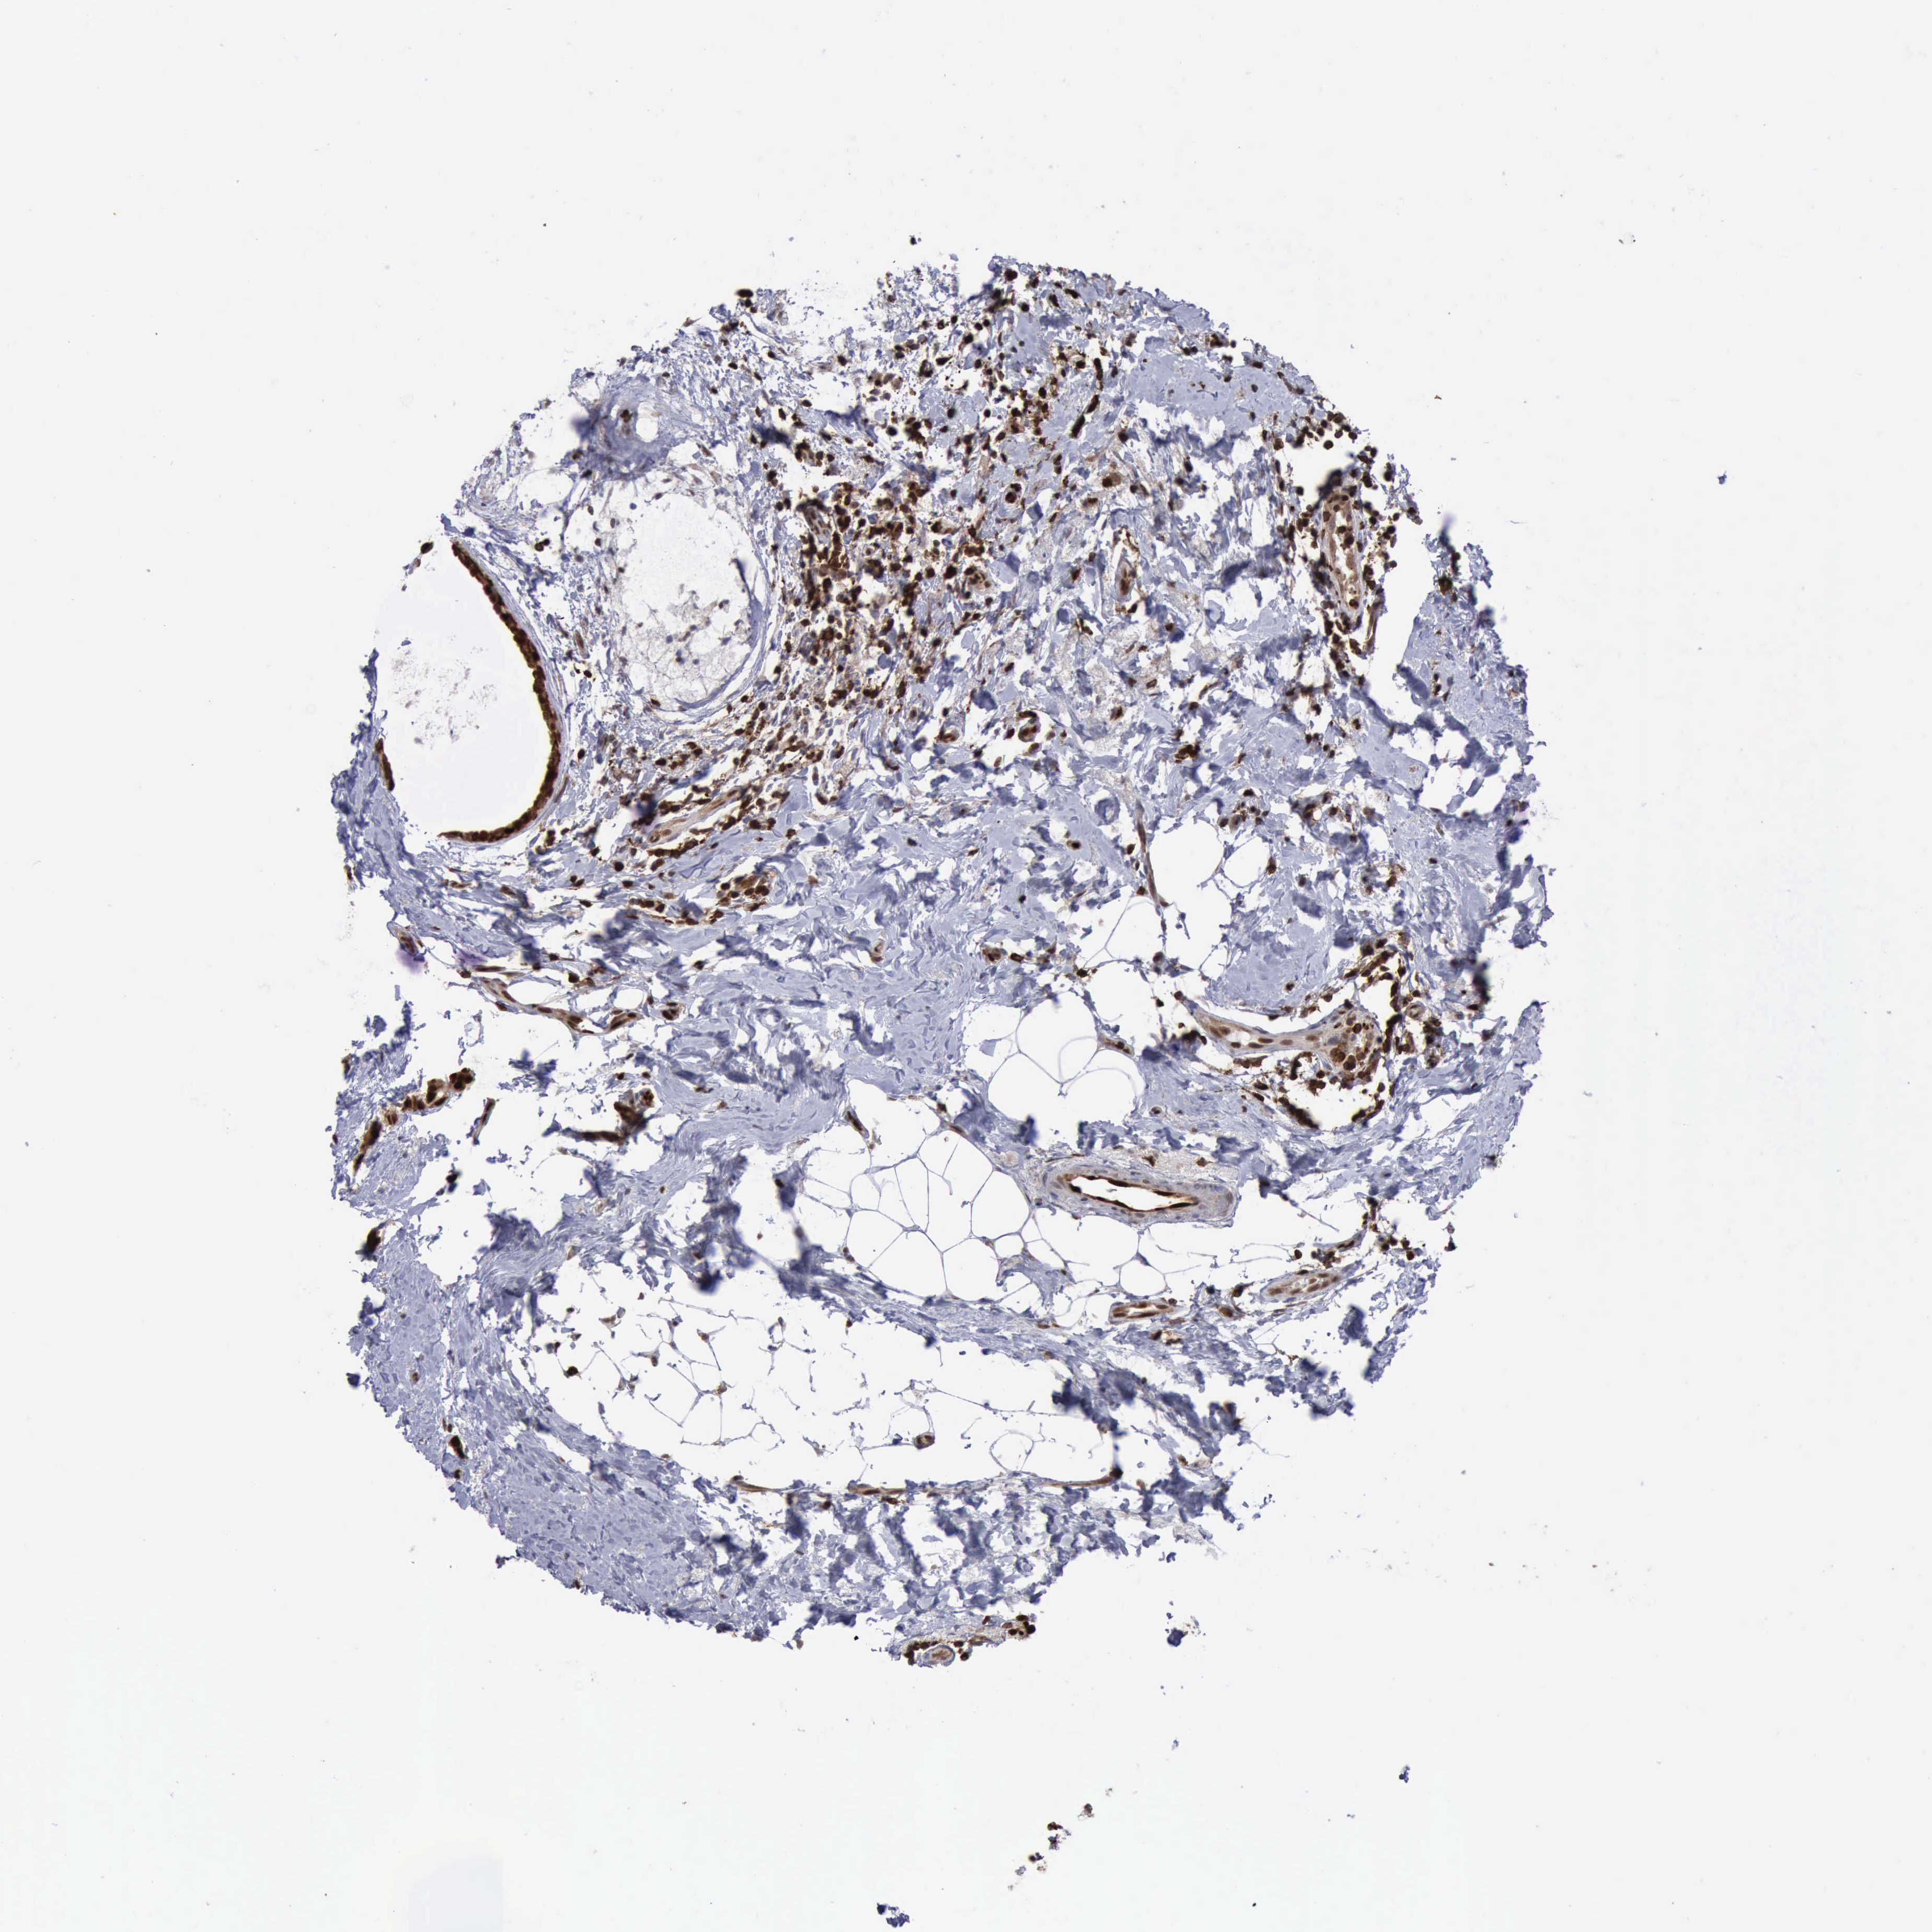

CANCER BREAST CANCER Show tissue menu

BRCA TCGA BRCA VALIDATION PROTEIN EXPRESSION

Breast cancer

Human cancer